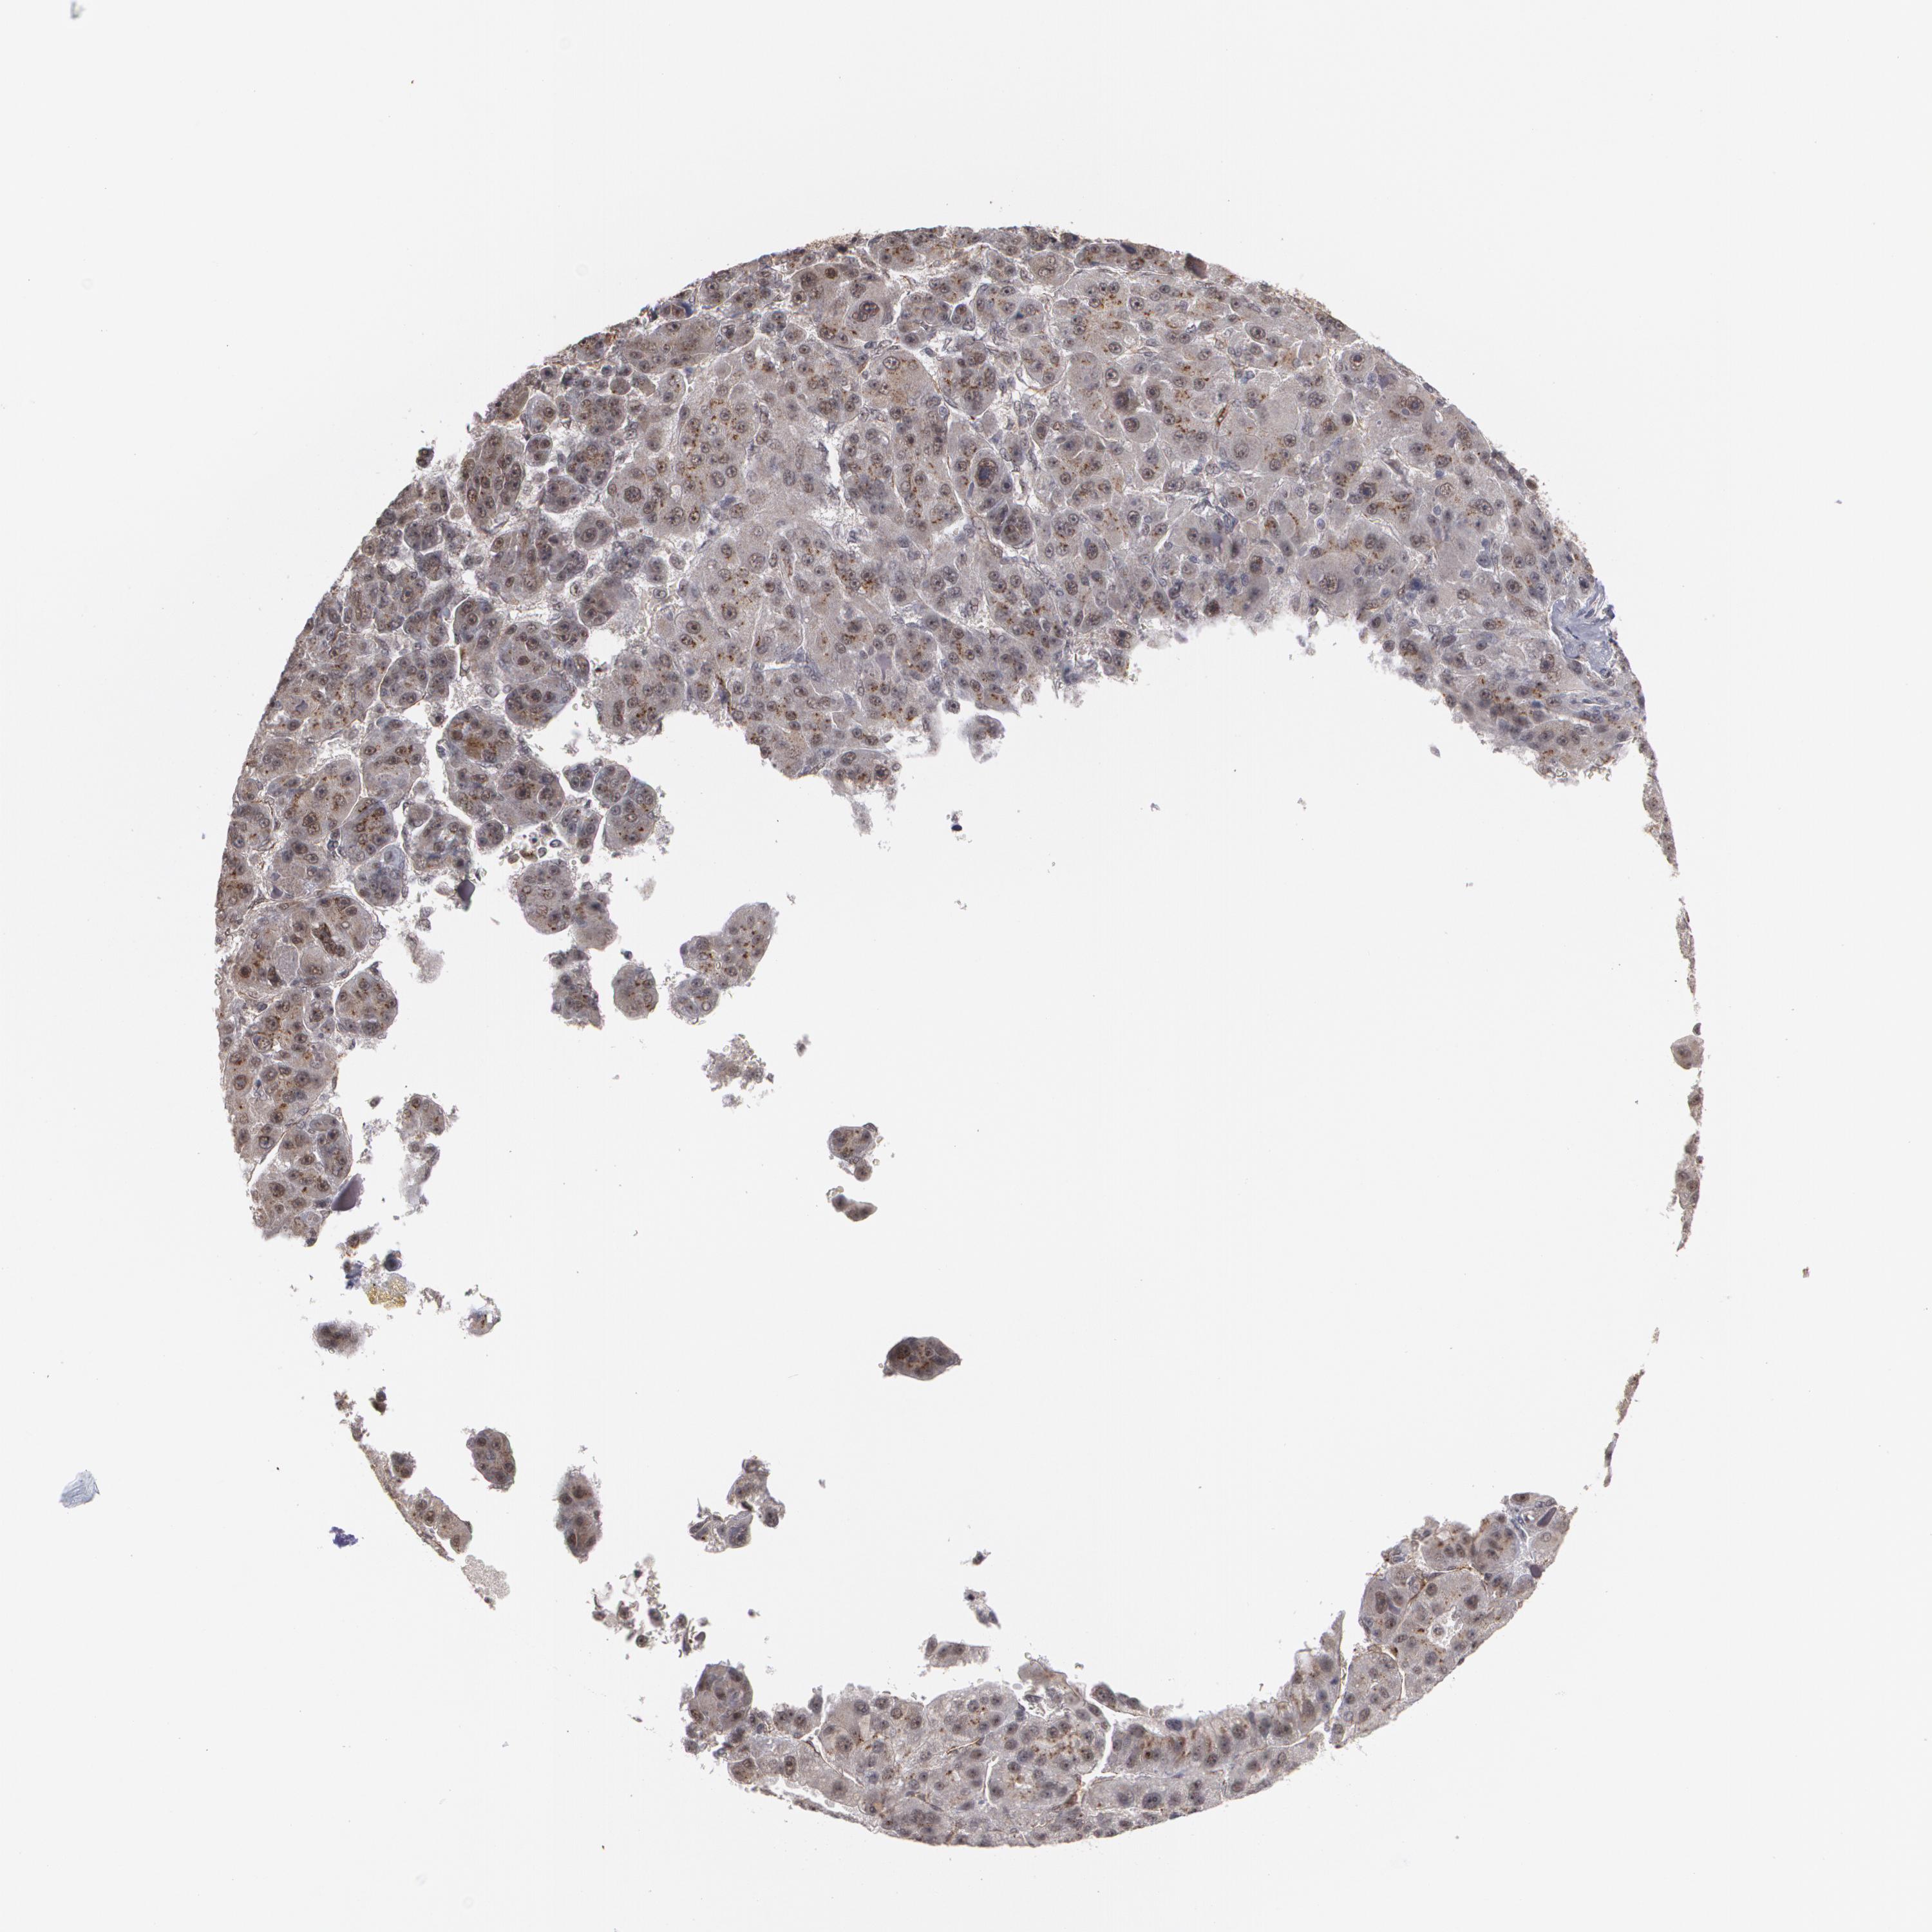

LIVER CANCER - Protein expressioni

A mouse-over function shows sample information and annotation data. Click on an image to view it in a full screen mode. Samples can be filtered based on level of antibody staining by selecting one or several of the following categories: high, medium, low and not detected. The assay and annotation is described here.

Note that samples used for immunohistochemistry by the Human Protein Atlas do not correspond to samples in the TCGA dataset.

Antibody stainingi

Antibody staining in the annotated cell types in the current human tissue is reported as not detected, low, medium, or high, based on conventional immunohistochemistry profiling in selected tissues. This score is based on the combination of the staining intensity and fraction of stained cells.

Each image is clickable and will lead to virtual microscopy that enables deeper exploration of all samples and also displays staining intensity scores, fraction scores and subcellular localization as well as patient and tissue information for each sample.

Antibody HPA001665

Staining

High

Medium

Low

Not detected

Intensity

Strong

Moderate

Weak

Negative

Quantity

>75%

75%-25%

<25%

None

Location

Nuclear

Cytoplasmic/membranous

Cytoplasmic/membranous,nuclear

Cholangiocarcinoma

Carcinoma, Hepatocellular, NOS